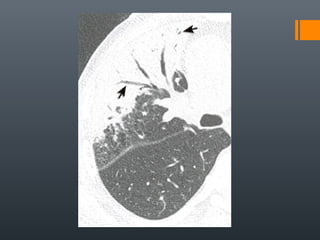

O documento discute vários conceitos radiológicos incluindo consolidação, atelectasia, nódulos, pseudocavidades e padrões intersticiais, fornecendo definições, sinais e diagnósticos diferenciais para cada tópico. Ele também discute a redução da atenuação pulmonar e fornece um link para mais informações.